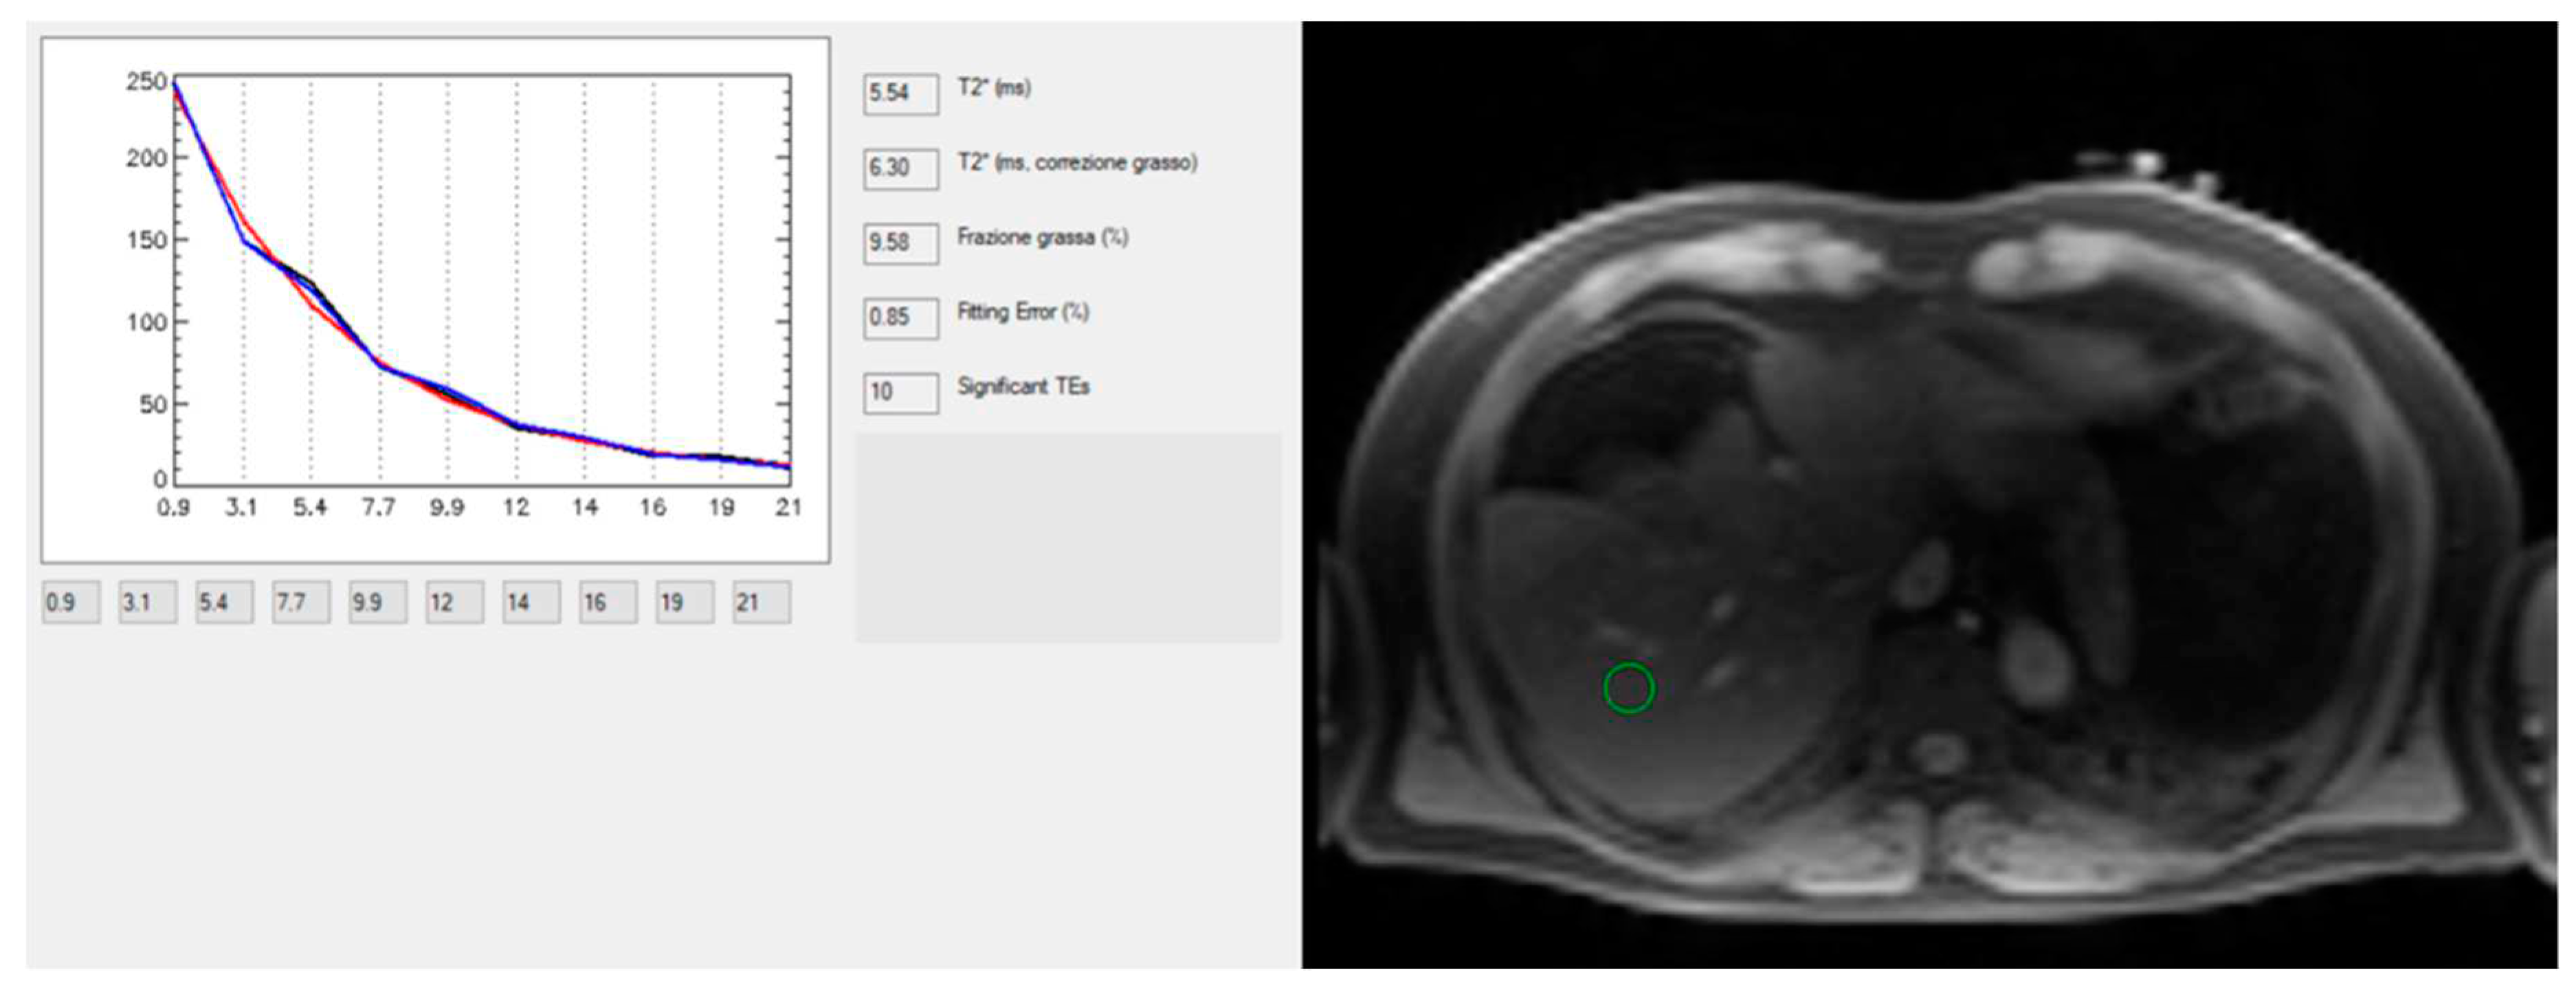

Technological advances of MRI for the study of chronic liver diseases have been proved also for the quantification of hepatic iron concentration, which may occur in hereditary hemochromatosis (i.e. the most prevalent genetic disease in the Caucasian population of North European origin), or secondary hemochromatosis (i.e. Italy is in the black belt of high prevalence for hemoglobinopathies). MRI provides a quantitative and safe, noninvasive approach to determine liver iron concentration (LIC). LIC may be calculated using signal intensity ratio (SIR), and R2- and R2*-based relaxometry methods. But nowadays, the last one is recognized as state-of-the-art method for accurate, validated, reproducible, and fast quantification of LIC (Positano et al., 2009) at both 1.5 T and 3 T (Meloni et al., 2012) .

MRI does not enable direct measurement of iron, but rather helps estimating the iron concentration indirectly through the effects of iron on the rate of proton signal decay. Therefore, any effect that alters the apparent signal decay rate, such as fat, may be introduce a bias for iron estimation. In the recent years, methods for simultaneous fat-water separation and R2* mapping have been introduced that allow unconfounded R2* relaxometry in the presence of fat (Meloni et al., 2012; Positano et al., 2009) also providing simultaneous quantification of liver fat, which is advantageous in NAFLD [Figure 9].

Therefore, commercially available confounder-corrected R2*-based LIC quantification should be preferred for their accuracy and reproducibility in quantification of LIC, being also strengthened by presence of regulatory approval, and rapid acquisition time (Reeder et al., 2023).